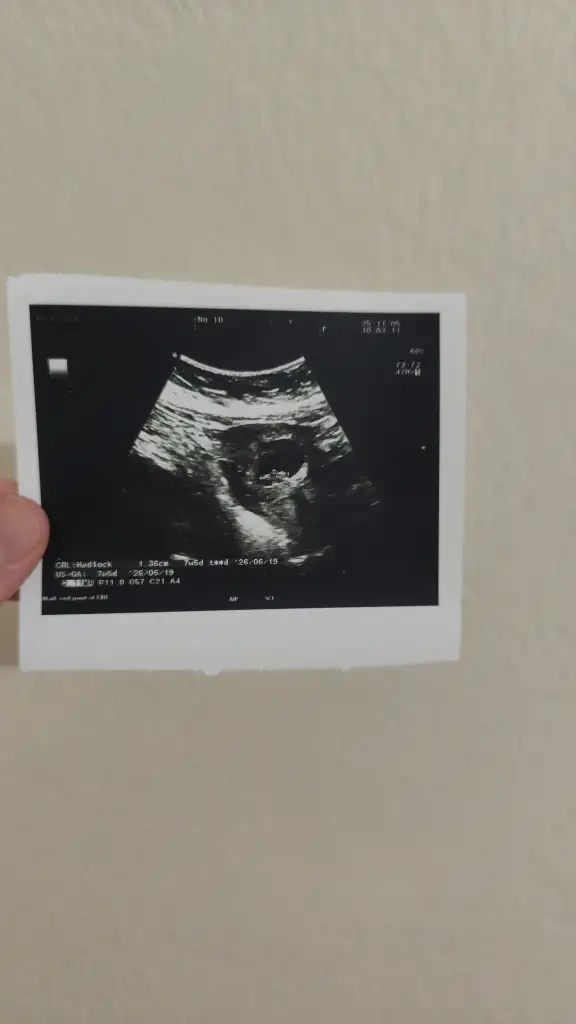

keseniz erkeğe benziyprCinsiyet belli olurmu kesenin şekline bakarak anlıyorlar ya kizlar yorum yapın bakalım ikinci hamilelik geçiren tecrübeli hamisler8+3 suanki kese

Teyzeler 7+5 olmuşuz çok şükür bugün kalp atışı duyduksizce cinsiyeti ne ?

sizin yuvarlak gıbı kıza benzıyorsemocann benimkine de bakar mısınız